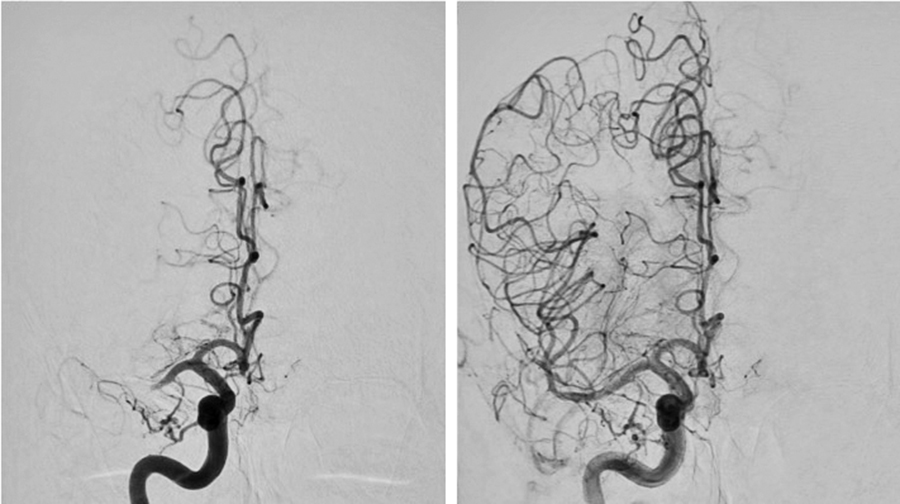

Mekanisk trombektomi vid akut ischemisk stroke förväntas öka